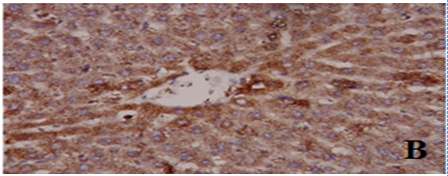

Fig. 7: Examination of the expression of nuclear factor Kappa B (NF-kB) in liver I, and kidney tissue II, using immunohistochemical staining following the administration of zinc oxide nanoparticles (ZnO NPs) and/or aluminum chloride (AlCl3) for 6 w (magnification 400 ×). A) control, B) aluminum chloride, C) zinc oxide nanoparticles and D) aluminum chloride+zinc Oxide nanoparticles

Effect of ZnO NPs and/or AlCl3 treatment on NF-κB expression

The immuno-reactivity of NF-κB was estimated in the hepato-renal tissue to follow the molecular mechanism of the anti-inflammatory effect of ZnO NPs. Rats intoxicated with AlCl3 showed overexpression of NF-κB, as compared to the control group. On the contrary, expression of NF-κB was down-regulated markedly in ZnO NPs and ZnO NPs+AlCl3-treated rats, when compared against AlCl3-treated rats. These findings indicate the anti-inflammatory activity of ZnO NPs used dose (fig. 7).